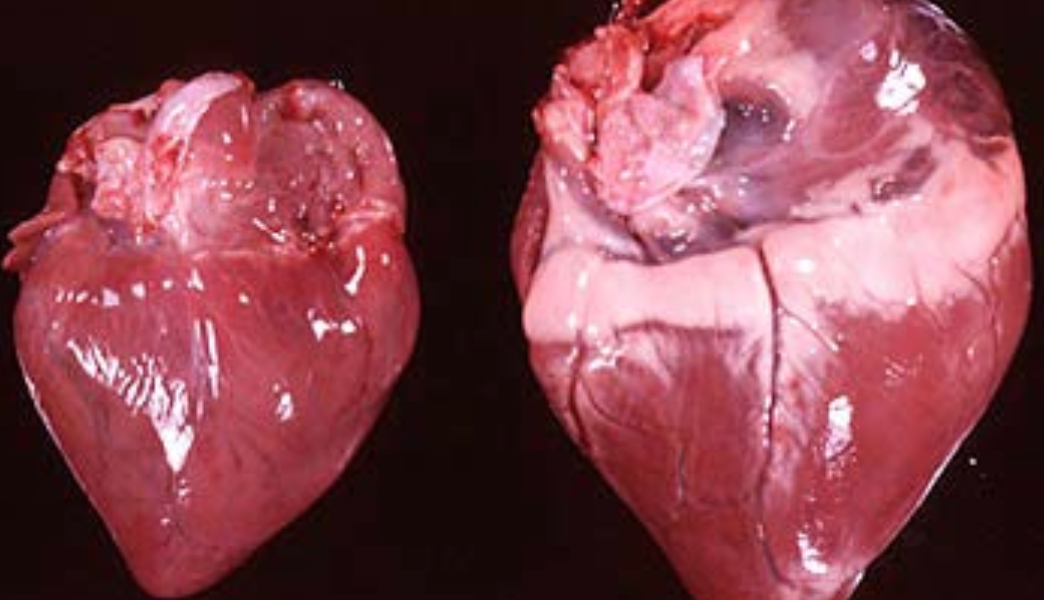

Concentric Hypertrophy

growth of a hollow organ without overall enlargement, in which the walls of the organ are thickened and its capacity or volume is diminished.

Hypertrophic cardiomyopathy (HCM) is common in ____________.

Hypertrophic cardiomyopathy (HCM) is common in Main Coon Cats.

Hypertrophic cardiomyopthy (HCM) in cats is due to a mutation in the____________.

Hypertrophic cardiomyopthy (HCM) in cats is due to a mutation in the MYBPC3 gene.

__________________________

Inherited autosomal dominant

Adaptation Response

(Normal = Left)

Atrophy